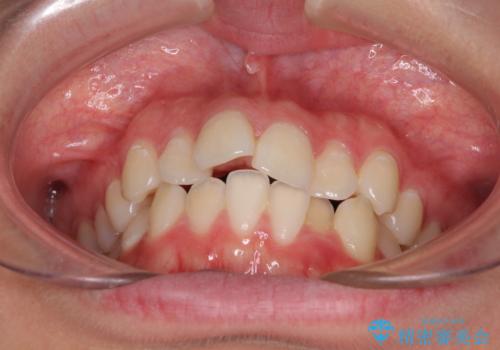

- 口元のデコボコを気にして来院された患者様です。

前歯の捻れにより口元が閉じにくくなっていたため、歯列全体の側方への拡大と、歯と歯の間を少し削ってスペースを獲得することとしました。